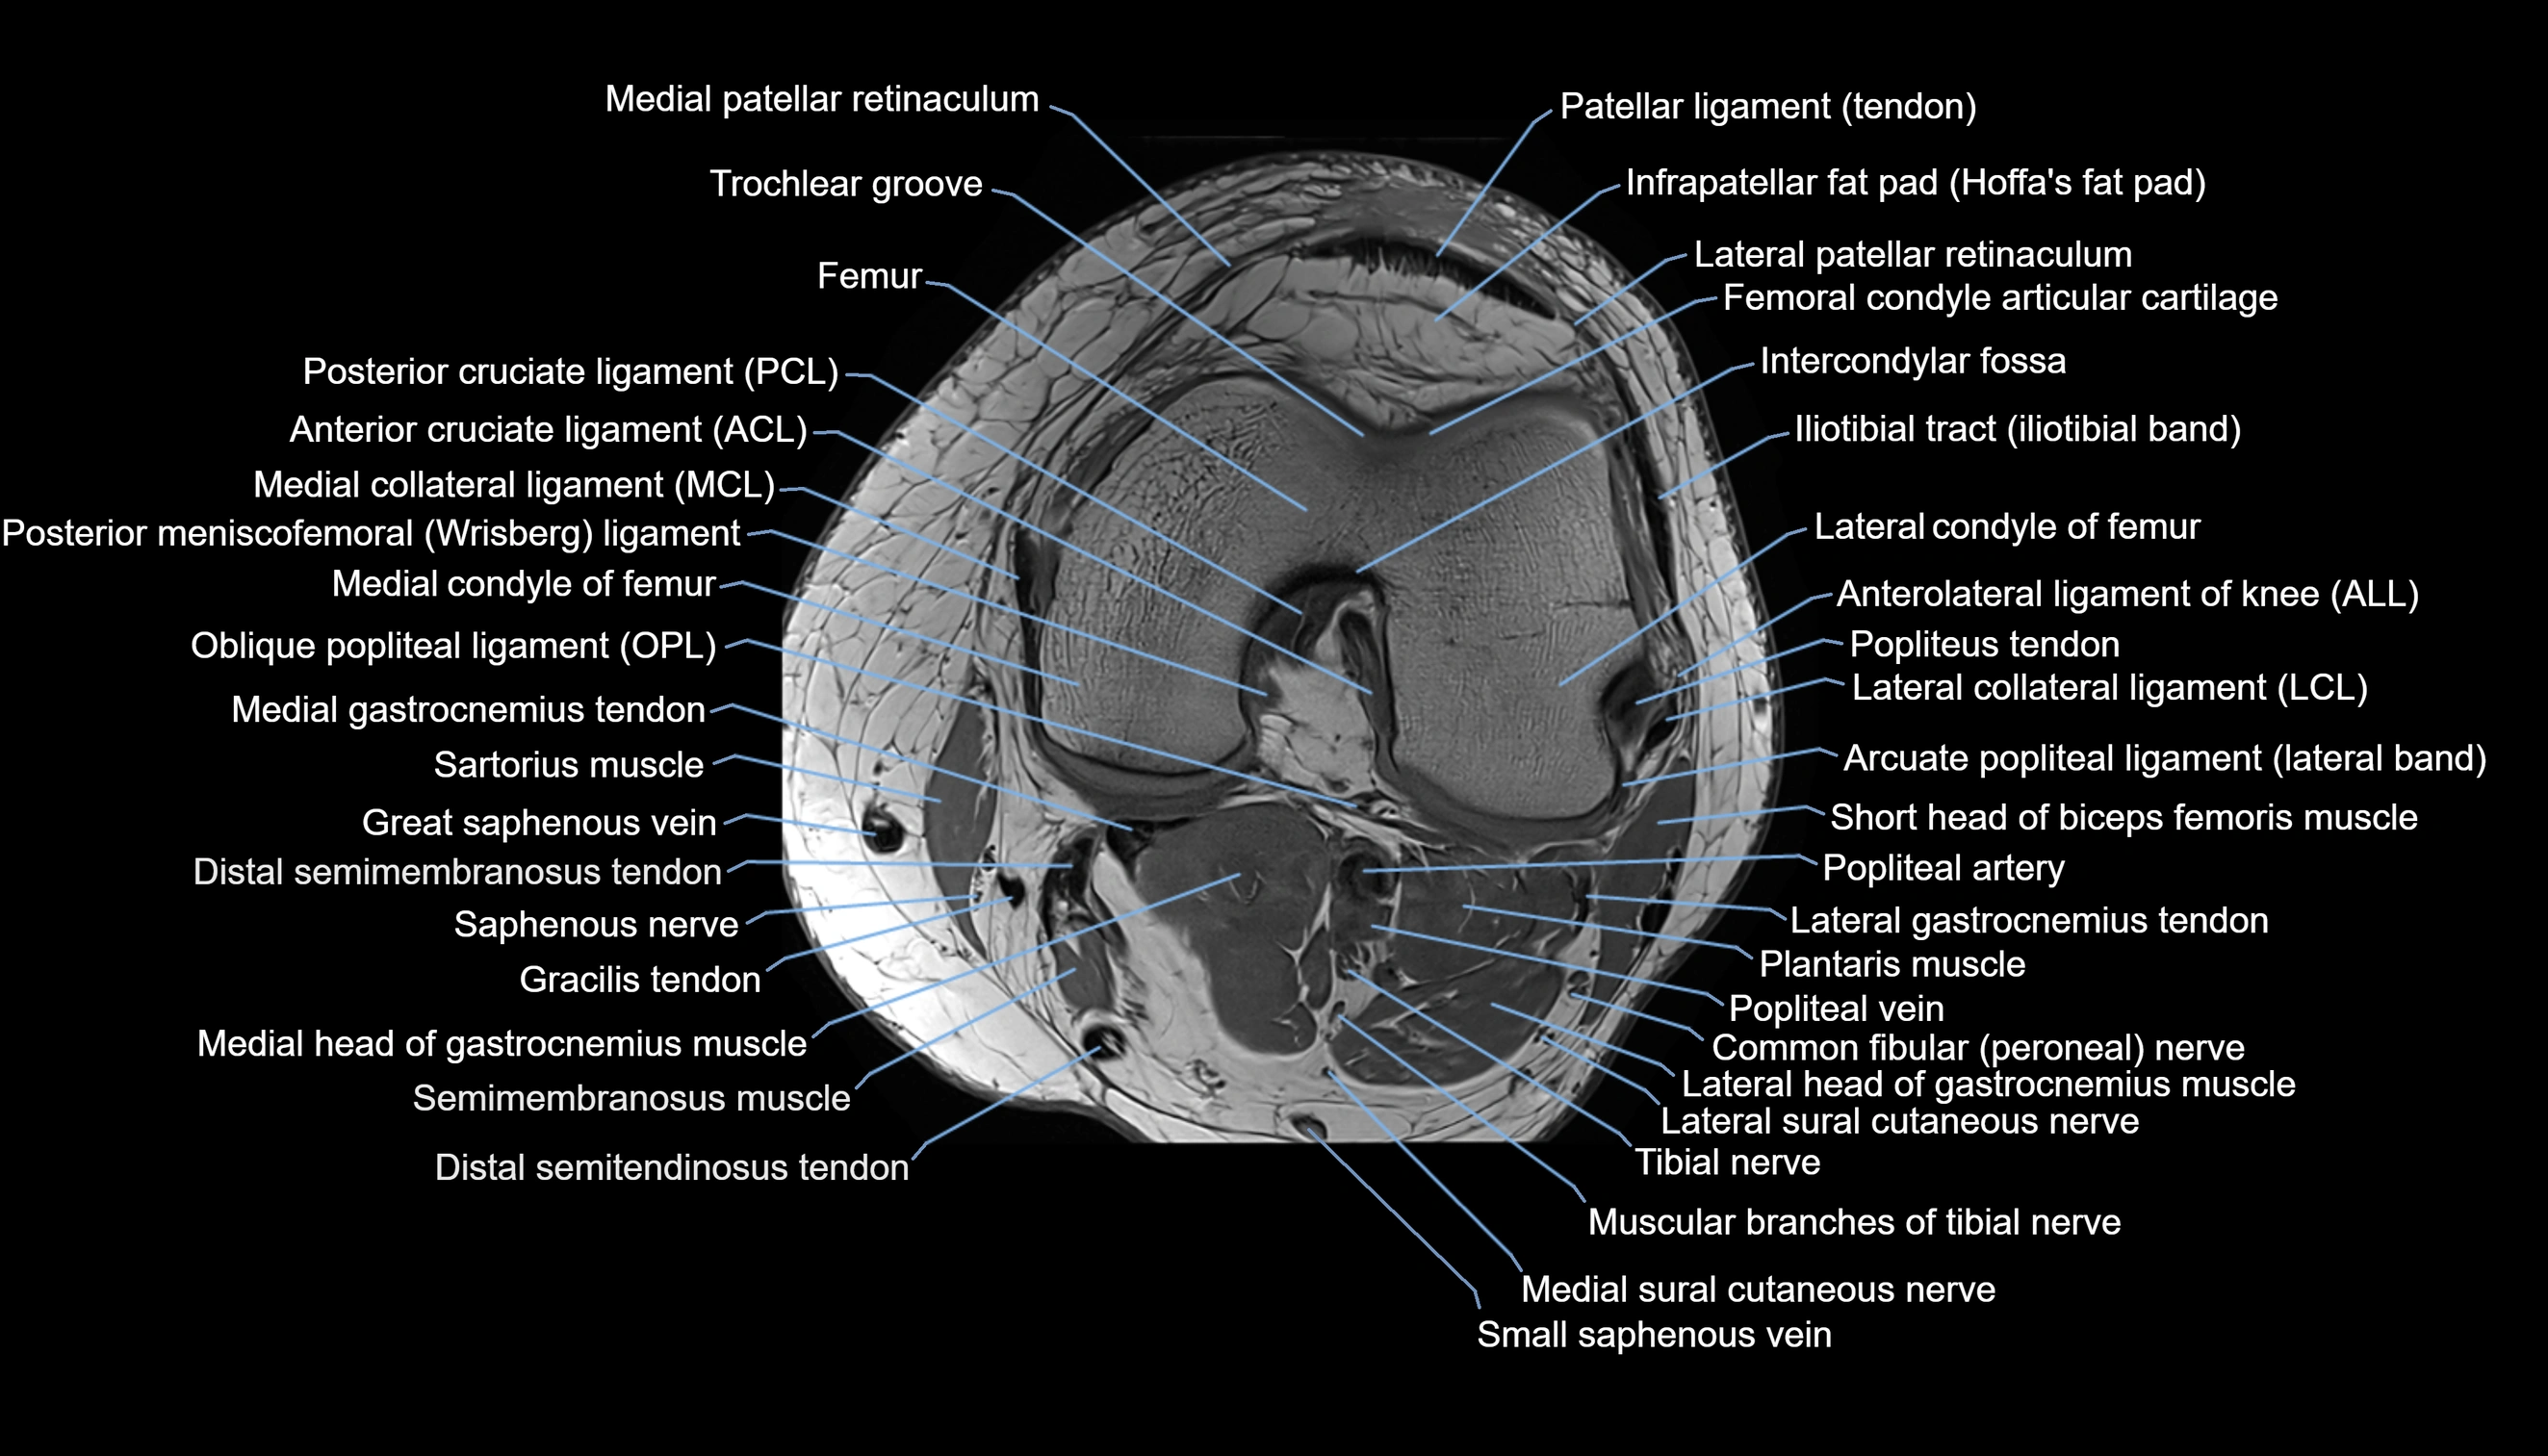

- Anterolateral ligament of knee

- Arcuate popliteal ligament

- Common fibular nerve

- Femoral condyle articular cartilage

- Infrapatellar branch of saphenous nerve

- Infrapatellar fat pad

- Intercondylar fossa

- Lateral collateral ligament

- Lateral condyle of femur

- Lateral gastrocnemius tendon

- Lateral head of gastrocnemius muscle

- Lateral patellar retinaculum

- Lateral sural cutaneous nerve

- Medial collateral ligament

- Medial condyle of femur

- Medial gastrocnemius tendon

- Medial head of gastrocnemius muscle

- Medial patellar retinaculum

- Medial sural cutaneous nerve

- Muscular branches of tibial nerve

- Oblique popliteal ligament

- Patellar tendon (patellar ligament)

- Popliteal artery

- Popliteal lymph nodes

- Popliteal vein

- Popliteus tendon

- Posterior cruciate ligament

- Posterior meniscofemoral ligament

- Saphenous nerve

- Sartorius muscle

- Semimembranosus muscle

- Small saphenous vein

- Tibial nerve